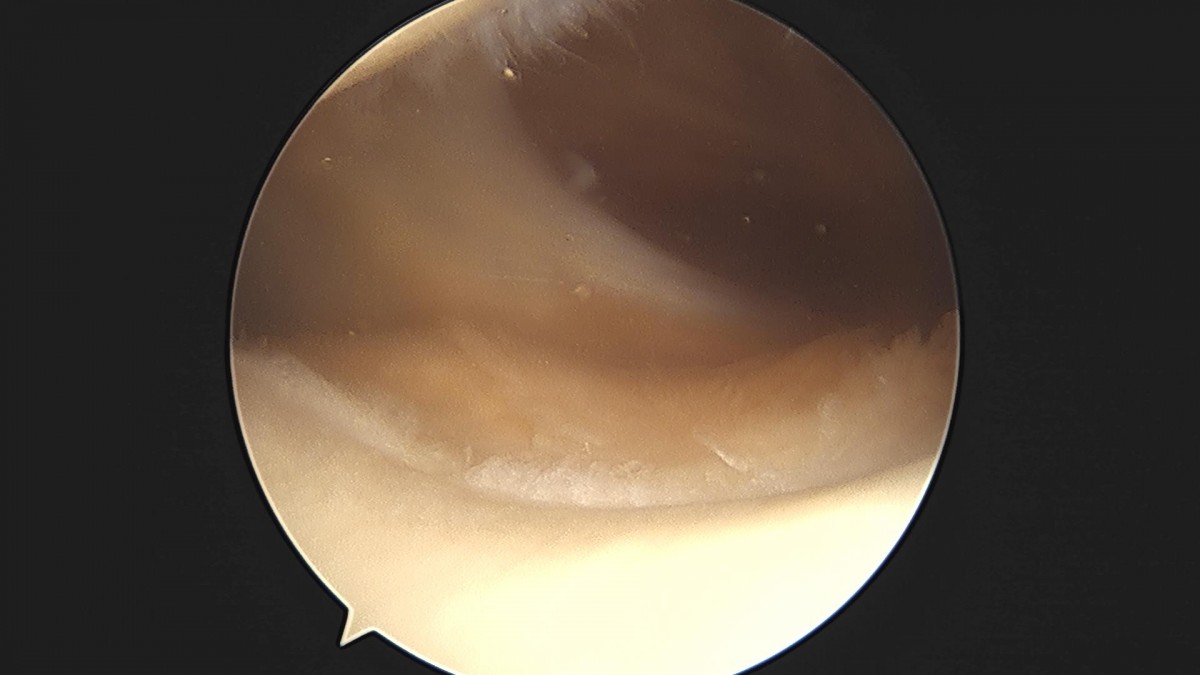

배우한원장님 무릎 반월상연골판 절제술 박대O 환자

작성자 최고관리자 댓글 0건 조회 2,233회 작성일 23-01-12 18:00